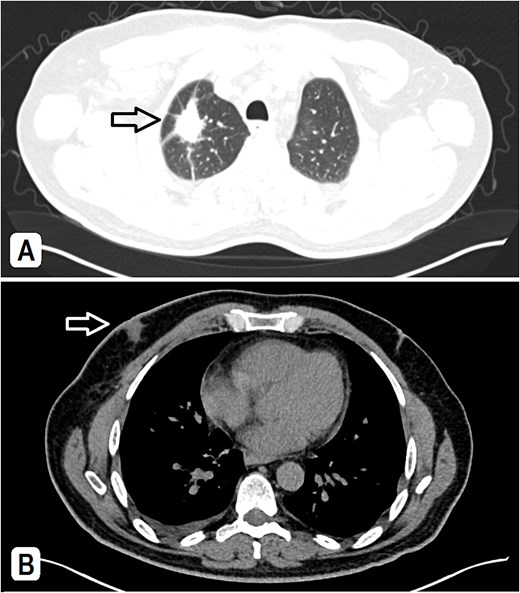

A 56-year-old male patient, married with four offspring, non-smoker, with free past medical and surgical history, presented to his family doctor complaining of a self-palpable, painless lump in the right submandibular area for 1-month duration. Family history included a brother with colon cancer. On examination, a right submandibular lump was noted, measuring ~2 cm, there is also a single painless, retro-areolar palpable breast lump with multiple right palpable lymph nodes. There were no skin or nipple changes. Neck ultrasound revealed right submandibular lymph node enlargement with bilateral prominent suspicious cervical lymph nodes. A CT scan showed a spiculated lesion in the right lung apex with adjacent atelectatic bands, pathologically enlarged hilar, mediastinal, and right-sided axillary lymph nodes. Additionally, there is noted asymmetry of breast tissue with right-sided retro-areolar soft tissue density (Fig. 1A and B). A positron emission tomography (PET) scan emphasized hypermetabolic, mildly prominent, multilevel cervical lymph nodes with intense fluorodeoxyglucose (FDG) uptake (SUVmax 13.3), extending to bilateral supra and right infraclavicular fossae, with the largest node in the right level 1 measuring 1.5 × 1.3 cm. A hypermetabolic right pulmonary apical soft tissue lesion was noted, measuring 2.9 × 2.4 cm with adjacent atelectatic bands, associated with hypermetabolic mediastinal and right axillary lymph nodes with intense FDG uptake (SUVmax 7.2) (Fig. 2A and B).

(A) A CT scan showed a spiculated lesion in the right lung apex with adjacent atelectatic bands, pathologically enlarged hilar, mediastinal, and right-sided axillary lymph nodes, the largest measuring 1.5 cm. (B) The mediastinal window of CT at the chest level shows an asymmetry of breast tissue with right-sided retro-areolar soft tissue density.